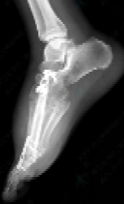

手术当天,麻醉手术部阳婷婷医生凭借丰富临床经验,顺利完成椎管内麻醉。在韩学哲与边卫国教授的指导下,杨卫周与刘俭涛医生精准切除受累的第一跖骨与内侧楔骨,并与整形外科何林医生顺利切取长约11厘米的小腿处带血管蒂腓骨,再通过“移花接木”式技术,将其移植至脚趾缺损部位。通过精细的显微外科技术,团队成功吻合足背血管,恢复移植骨块血运。在多科室通力协作下,手术圆满完成。